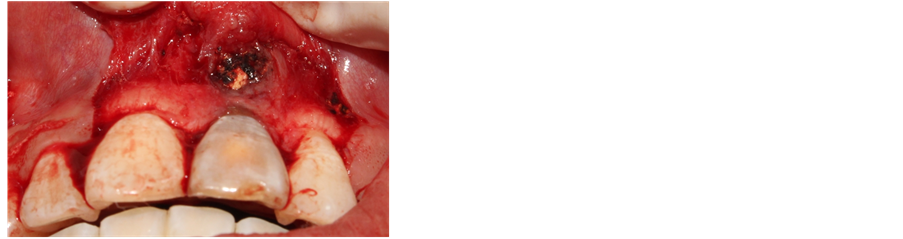

Therapeutic methods: 1) another root canal therapy was conducted for the 21st tooth to measure the length with endometer. However, root filling condition cannot be judged with the foreign body at apex by X ray, so operation of apex should be conducted immediately after root filling. 2) Crevicular incision. Crumby matter can be seen at apex in flaple. The matter was taken out from the apex (the texture is hard and elastic as hot gutta-percha with diameter of about 8

mm (Figures 4-6). 3) Scratch the apex and wash it with normal saline. Restore and suture the mandibular with minocycline smeared in partial (Figure 7). 4) Post-operative CBCT shows that root filling was improved and the resistant projection of agglomerate at apex disappeared (Figures 8-9). 5) Fistula disappeared 1 week after operation (Figure 10). 6) Intracoronal bleaching was conducted and then medical prescription was changed twice in follow-up visit. The color of 21st tooth became 11 and 12 with resin repair at the incisal margin of 21st tooth. 7) The color change of bleaching opisthosoma is relatively obvious than that in neck. The color of tooth neck is dark. The protective screen was established for the third bleaching. Four days later, further consultation was conducted with color of tooth neck improved. The patient was satisfied (Figure 11). 8) 1, 3, 6 and 12 months after operation, further consultation was conducted in follow-up (Figure 12).

Figure 4. Open and flap the root tip of the and low density mass.